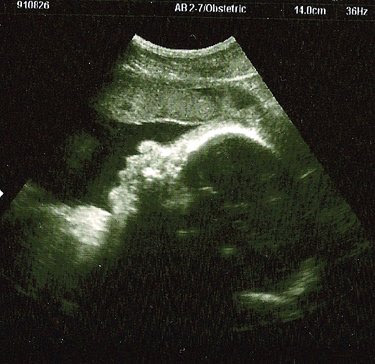

…there’s that sweet little head. We had an ultrasound on Tuesday to take a look at the fluid level around the baby (I had low fluid with E) and they wanted to start a bit earlier in the monitoring. Things looked pretty good this time around – they were looking for the magic number of 10, and we were just above that. We got a free pass for a few weeks, but will begin weekly monitoring after that so we’ll be seeing a lot more of this little one then. After checking and rechecking the numbers, we got to stick around for a little show. Not only was the baby awake, but it was opening and shutting its eyes and mouth – little gestures that reminded us of the way a baby looks right after they wake up and they are just peacefully looking around the room checking things out. We knew from our pregnancy journal that the eyelids were no longer fused, but it was still so strange to see the eyes open and moving. I’m not sure what there is to “see” in there, and the baby has no way yet to process images – but it is clearly practicing all those reflex movements that will help it figure out this world once it enters it. Towards the end of the show the baby yawned the sweetest, most perfect little yawn. It made all those kicks and jabs and uncomfortable moves in the night a little less bothersome once we saw that little one just gently moving and adjusting to its shrinking environment. Why should I complain or gasp every time one of these movements throws me off balance or connects with some tender organ of my own – look at this sweet little thing in there, just practicing those muscle movements and trying to find some space?

Front of face (sideways with forehead on your right, eyes and mouth in shadow)